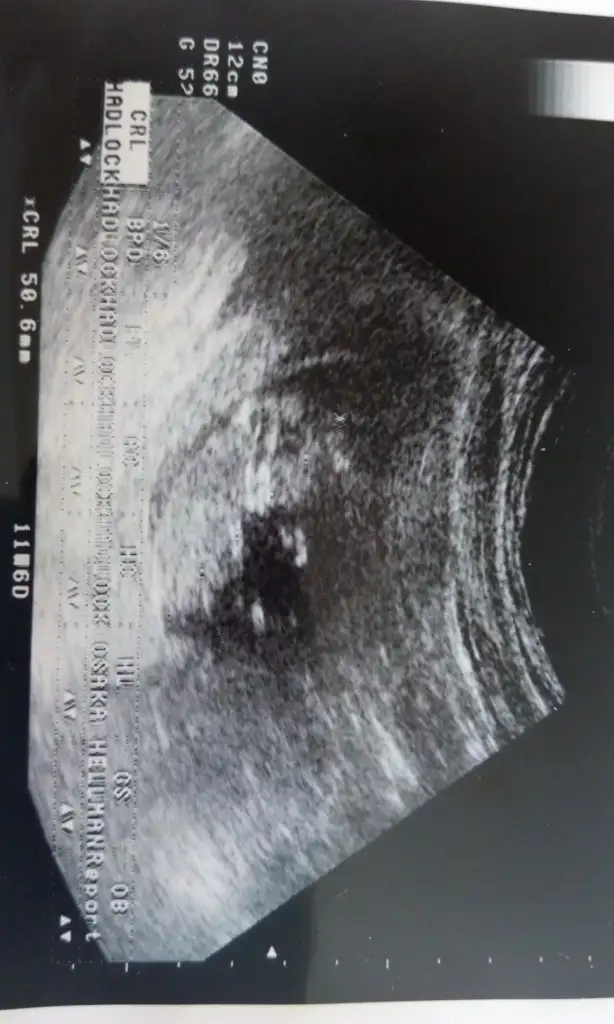

Az önce ultrasonda n çıktım 13+4

Doktorum cinsiyet kesin değil ama kız gibi dedi sizlerden yorum bekliyorum lütfen ☺☺Eki Görüntüle 1468173

Canim bugun gittim doktoruma cok israr ettim ama soylemedi tahmin bile etmedi onumuzdeki ay soylerim dedi hayirlisi artikÇıkıntı yok nun çizgisi parelel kordonu parelel bu teoriye göre kız olmasi lazım ama benim içimden erkek gecti hayırlısi öğrenince yaz merak ettim